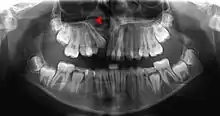

Pressure or pain in the jaw area can be associated with dilaceration. Checking in with a general dentist and an endodontist should be done if a patient feels these symptoms.[4] Signs in radiographic imaging will indicate a bend in the tooth's root as opposed to a straight growth.[1] Dilaceration of the crown, the top part of the teeth that we see when we smile, can be visually seen for diagnosis. Crown dilaceration will present itself as a tooth that is angled to face outward or inward. It will be a non axial displacement and more of a longitudinal displacement.[5]

Dilaceration can be diagnosed with a simple radiograph of the affected teeth. However, if the bends are more lingual or facially present,[1] more advance imaging techniques may be necessary. In some cases a cone-bean CT scan may be useful to create a three dimensional view.[9]